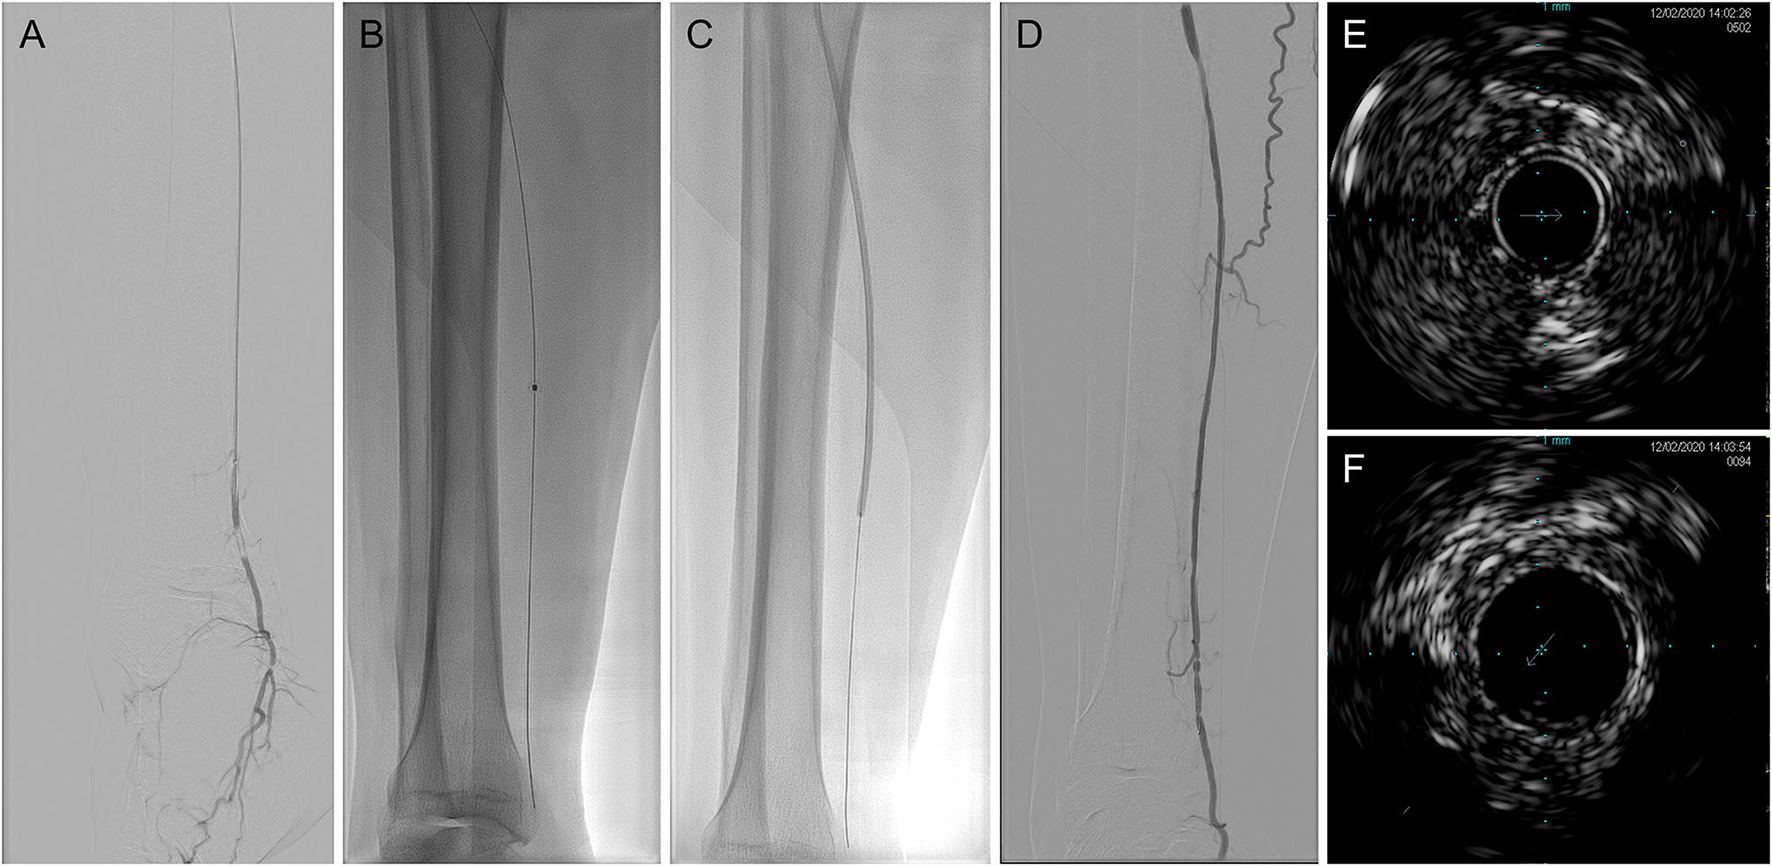

The procedural data of laser-assisted BA are summarized in Table 2. There was no significant difference in lesion length or target artery distribution between the technical success and technical failure groups. The average lesion length in patients who received the successful intervention was 34.05 ± 9.63 (range: 15–50) cm. Among the target arteries, the proportions of the anterior tibial artery, posterior tibial artery, and peroneal artery in the technical success group were 45.95, 43.24, and 10.81%, respectively. In contrast, the proportion of peroneal arteries in the technical failure group was larger than that in the technical success group (without significance, p = 0.0525). The mean maximum fluency was 52.84 ± 4.00 (range: 45–55) mJ/mm2, and the total range was 30–60 mJ/mm2. The mean maximum repetition rate was 72.57 ± 6.83 (range: 60–80) Hz, and the total range was 25–80 Hz. After the intervention, the minimum vessel wall thickness measured by IVUS was 1.10 ± 0.29 (range: 0.52–1.53) mm. No artery perforation or distal embolization was observed. The representative case is shown in Figure 1.

Figure 1

Representative digital subtraction angiography (DSA) and intravenous ultrasound (IVUS) imaging of laser-assisted angioplasty intervention. (A) Baseline angiography; (B) excimer laser angioplasty; (C) balloon angioplasty (BA); (D) after intervention angiography; (E) baseline IVUS imaging; and (F) after intervention IVUS imaging. DSA, digital subtraction angiography; IVUS, intravenous ultrasound.